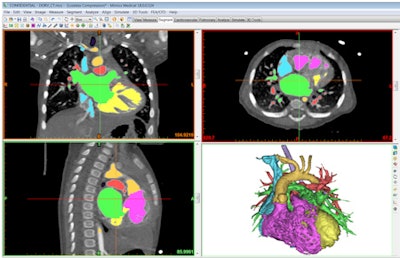

The considerations for preparing CT, MRI, or 3D ultrasound data for 3D printing are very different from traditional image processing and 3D volume-rendering techniques. Choose an appropriate software tool that has a strong combination of automated and manual segmentation functionality.

Often the cases that will benefit most from 3D printing are the most complex in terms of anatomical anomalies. This can challenge even the most sophisticated segmentation algorithms, so also find a tool that enables efficient manual intervention during segmentation when necessary.

In addition, it is useful to have a tool that can reconstruct and render your stereolithography (STL) files within the software instead of a simple STL export option. This gives you the advantage of seeing and verifying what you have created prior to 3D printing.

Segmenting the medical imaging is only half of the battle. Often, the more important and labor-intensive part of the 3D printing process is the further preparation and augmentation of your segmented anatomy. This can include features such as cleaning and smoothing to remove artifacts, adding connectors to hold anatomies in the proper anatomical positions, adding thickness to represent vessel walls, cutting of the model to achieve optimal visualization, and indicating color or multiple materials.

For a complex heart procedure, the surgeon will want to understand the intricacies of the intracardiac anatomy or landmarks for a specific valve or vessel. This will require you to prepare the heart model with windows or cut along a split line to achieve this visualization and separate components to identify another color in the model. Each application of 3D printing will have very different 3D modeling requirements.

Prior to printing, the accuracy of your final file should be verified against the original DICOM imaging. Did you oversmooth and remove a key feature from the model? Did you cut away a structure that would be an important landmark for the surgeon?

I would recommend a solution that allows the user to overlay the STL surfaces back on the DICOM data. This will allow you to verify accuracy (and convince others of it), as well as make subtle adjustments or refinements to the model.